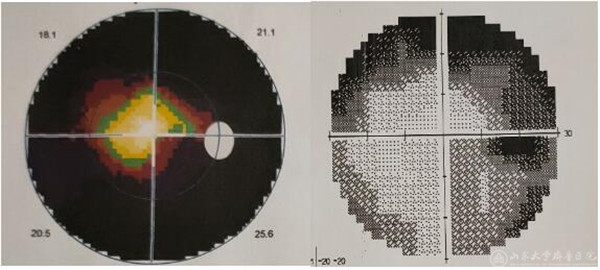

(术前及术后右眼视野的对比,可见明显改善)